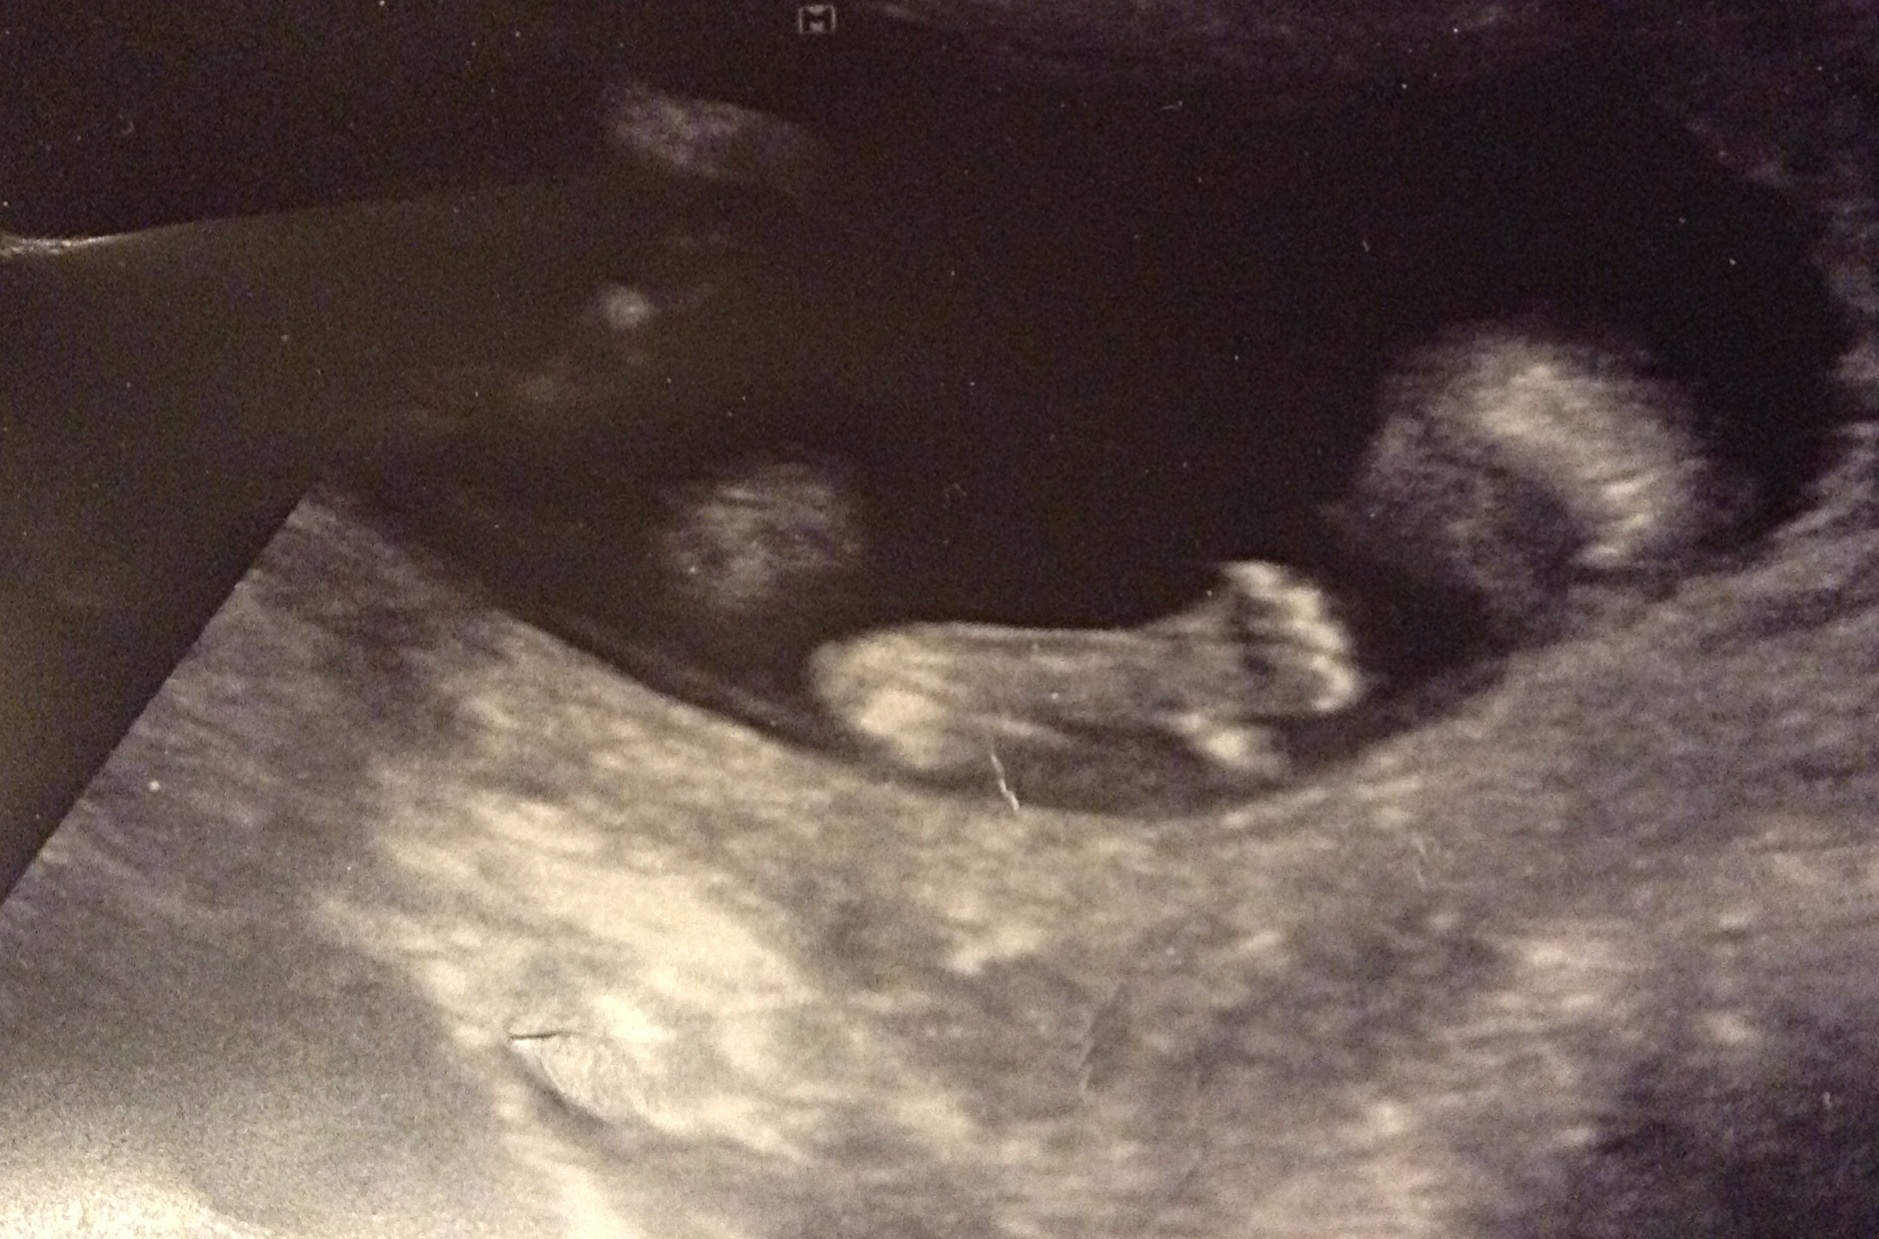

It's a little white dot/nub between babys legs, but I have no idea what it means. Do you? Attachment 8133

I don't see a nub.